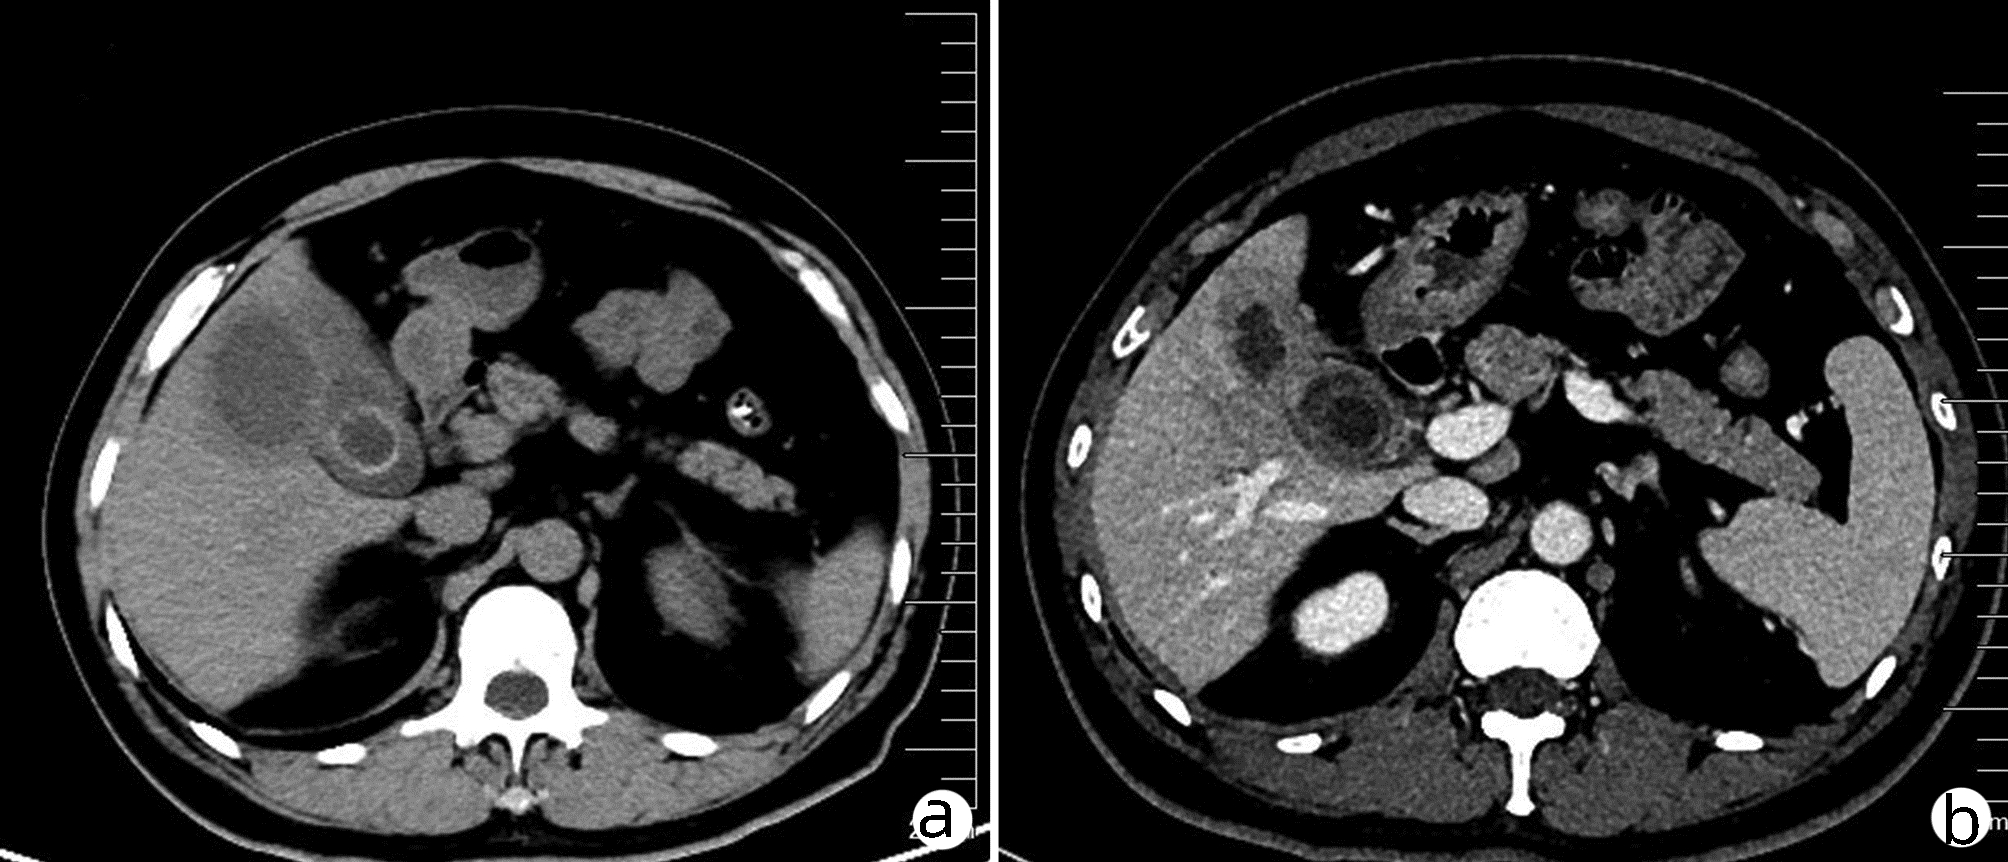

Liver abscess caused by type II gallbladder perforation: A report of 3 cases and literature review

Shaoxiong REN, Ze LIANG, Jingzhao HAN, Hongfang TUO, Yanhui PENG

2022, 38(4): 894-897. DOI: 10.3969/j.issn.1001-5256.2022.04.031

Abstract(1221) HTML (294) PDF (2784KB)(68)

Abstract: